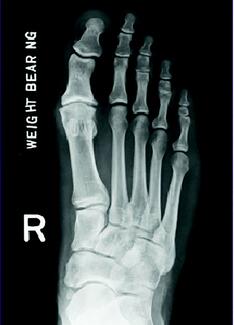

Nathan Ptak, DPM; Brady Mallory, DPM, FACFAS

In the case study presented, progressive correction and stability of the first ray was obtained without the addition of a Cotton osteotomy, in the presence of a flexible forefoot varus with a dorsiflexed first ray intraoperatively. This case...